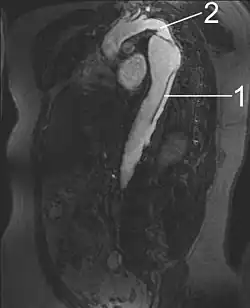

1 Aorta descendens with dissection

2 Aorta isthmus